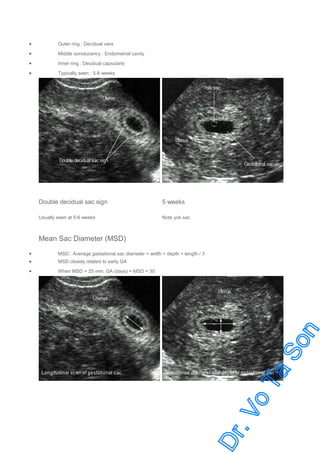

Double Decidual Sac Sign (DDS)

•

Strongly suggestive of intrauterine pregnancy

Outer ring : Decidual vera

Middle sonolucency : Endometrial cavity

Inner ring : Decidual capsularis

Typically seen : 5-8 weeks

Double decidual sac sign

5 weeks

Usually seen at 5-6 weeks

Note yok sac

Mean Sac Diameter (MSD)

MSD : Average gestational sac diameter = width + depth + length / 3

When MSD > 25 mm. GA (days) = MSD + 30

MSD closely related to early GA

Mean sac diameter

Longitudinal diameter

Transverse diameter and depth